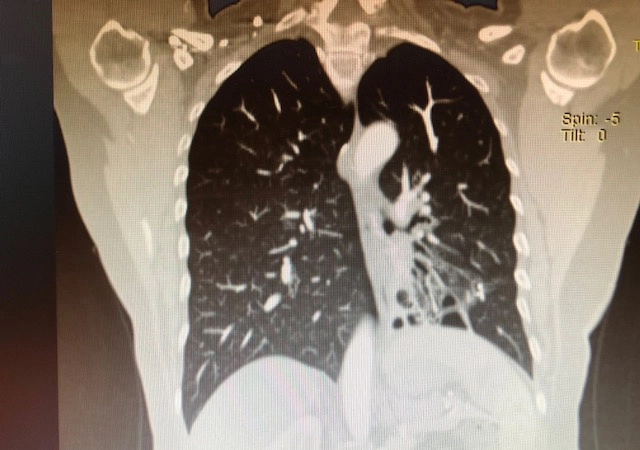

Konu ile ilgili bilgi veren Göğüs Cerrahisi Uzmanı Doç. Dr. Özkan Demirhan,” Soluk borusunun devamında ana bronş ve sonrasında bronşlar gelmektedir, bronş duvarının kas ve elastik yapısının bütünlüğünün bozulması sonucunda anormal ve kalıcı genişlemeye Bronşektazi denir. Bronşektazi doğumsal nedenlerden kaynaklanabileceği gibi sonradan da oluşabilir. Doğumsal nedenlerden kaynaklı Bronşektazi'de anatomik bozukluklar, damarsal bozuklular, solumun yolu üzerindeki silia tabakası bozuklukları ve immün sistem zayıflıkları rol oynar. Sonradan gelişen Bronşektazi'de ise sigaranın olumsuz etkilerinin yanı sıra sık geçirilen akciğer enfeksiyonları, bronşu tıkayan (yabancı cisim), bronşu daraltan durumlar ( bronş etrafında bulunan lenf bezelerinin bası yapması), aspirasyon pnömonisi gibi durumlar söz konusu olabilir. Bronşektazi en sık sol alt lobda görülmesine rağmen akciğerin tüm bronşlarını etkileyebilir” dedi.

Bronşektazi'nin tedavi şekline değinen Demirhan,” Bronşektazi hastaları önce göğüs hastalıkları uzmanına gidiyor. Uzun süre tedavi ediliyor. Rutin tedavi prosedürü de budur. Önce medikal tedavi olmuyorsa ameliyat düşünülür. Eğer medikal tedavilerde enfeksiyon dirençli hale geldi ve kurutmak imkansız ise bu durum da hastanın yaşam konforunu bozuyorsa ameliyat devreye girer. Yaygın Bronşektazi'lerde ameliyat önerilmiyor, Bronşektazi sınırlı yani lokalize ise daha iyi sonuç alınıyor. Cerrahide lokalize Bronşektazi hastalarına kapalı yöntemlerle videotorokoskopik veya robotik ameliyatlar yapıyoruz. Bu ameliyatlardan sonra hasta önemli ölçüde sağlığına kavuşabiliyor. Eğer hastalar ihmal eder ya da ameliyat gerektiren durumları geciktirirlerse enfeksiyon vücuda dağılıp apse gelişimine, Ampiyem'e, hemoptiziye (balgamdan kan gelmesine ), beyin apsesine ya da nadir de olsa sepsise neden olabilir” ifadelerini kullandı.